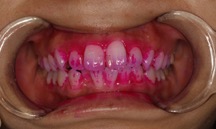

特殊な染料を使用して、歯の表面に付着した歯垢を検査します。これにより、日常の歯磨きで歯垢を効果的に除去できているかを評価します。必要に応じて、適切な歯ブラシの使用方法を指導することもあります。